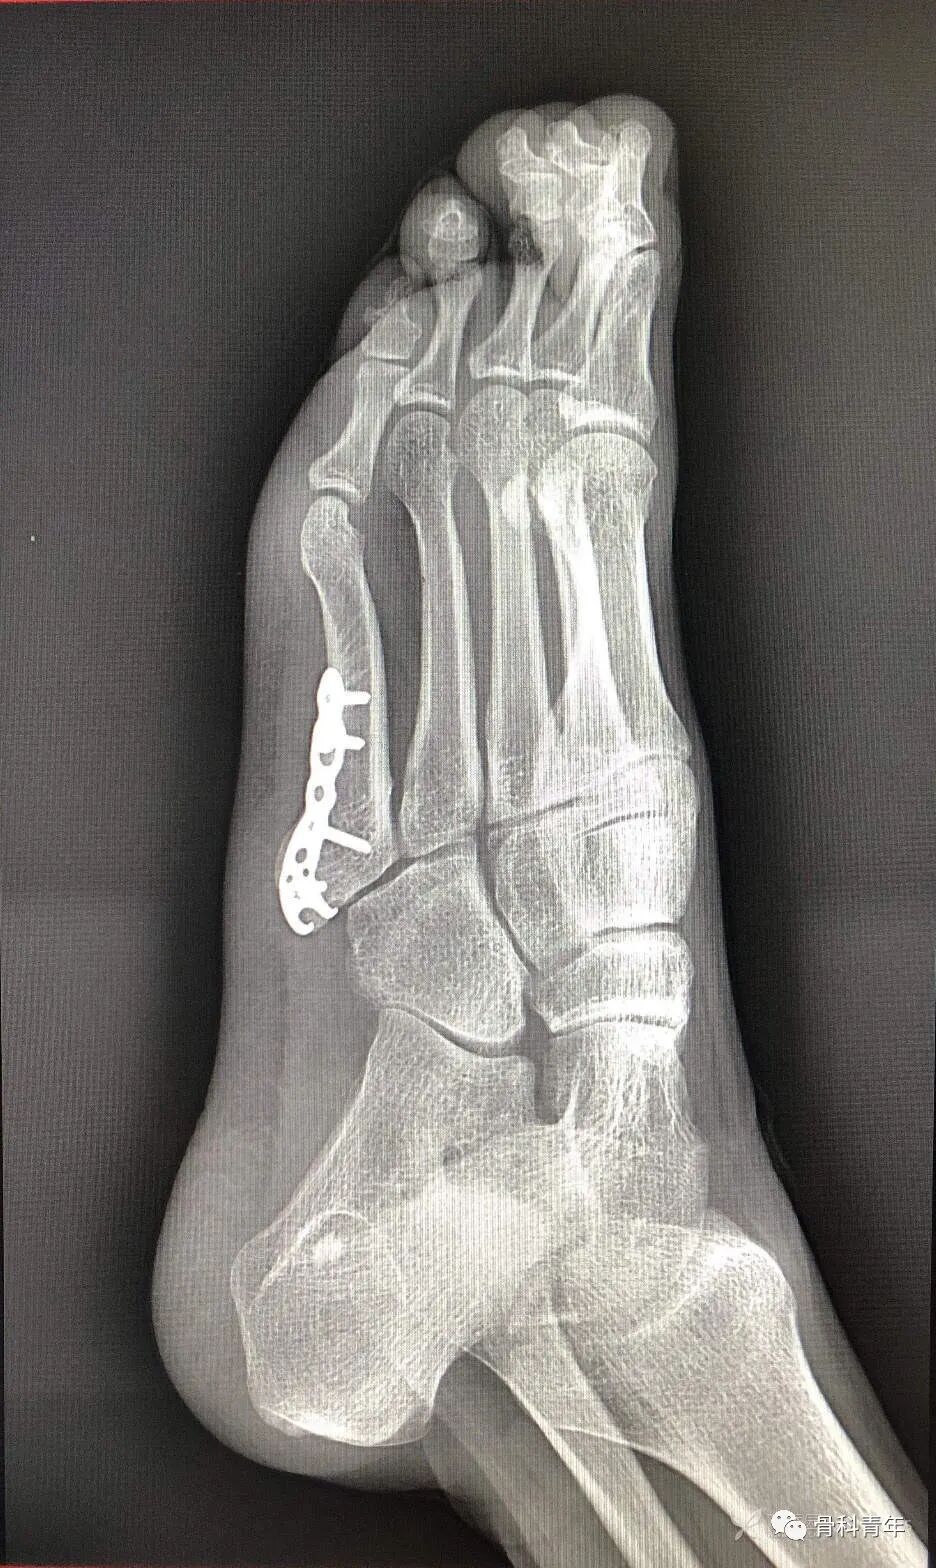

17.第五跖骨基底部骨折(钢板)